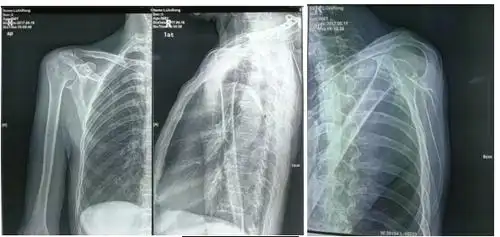

肩关节x线检查体位大全